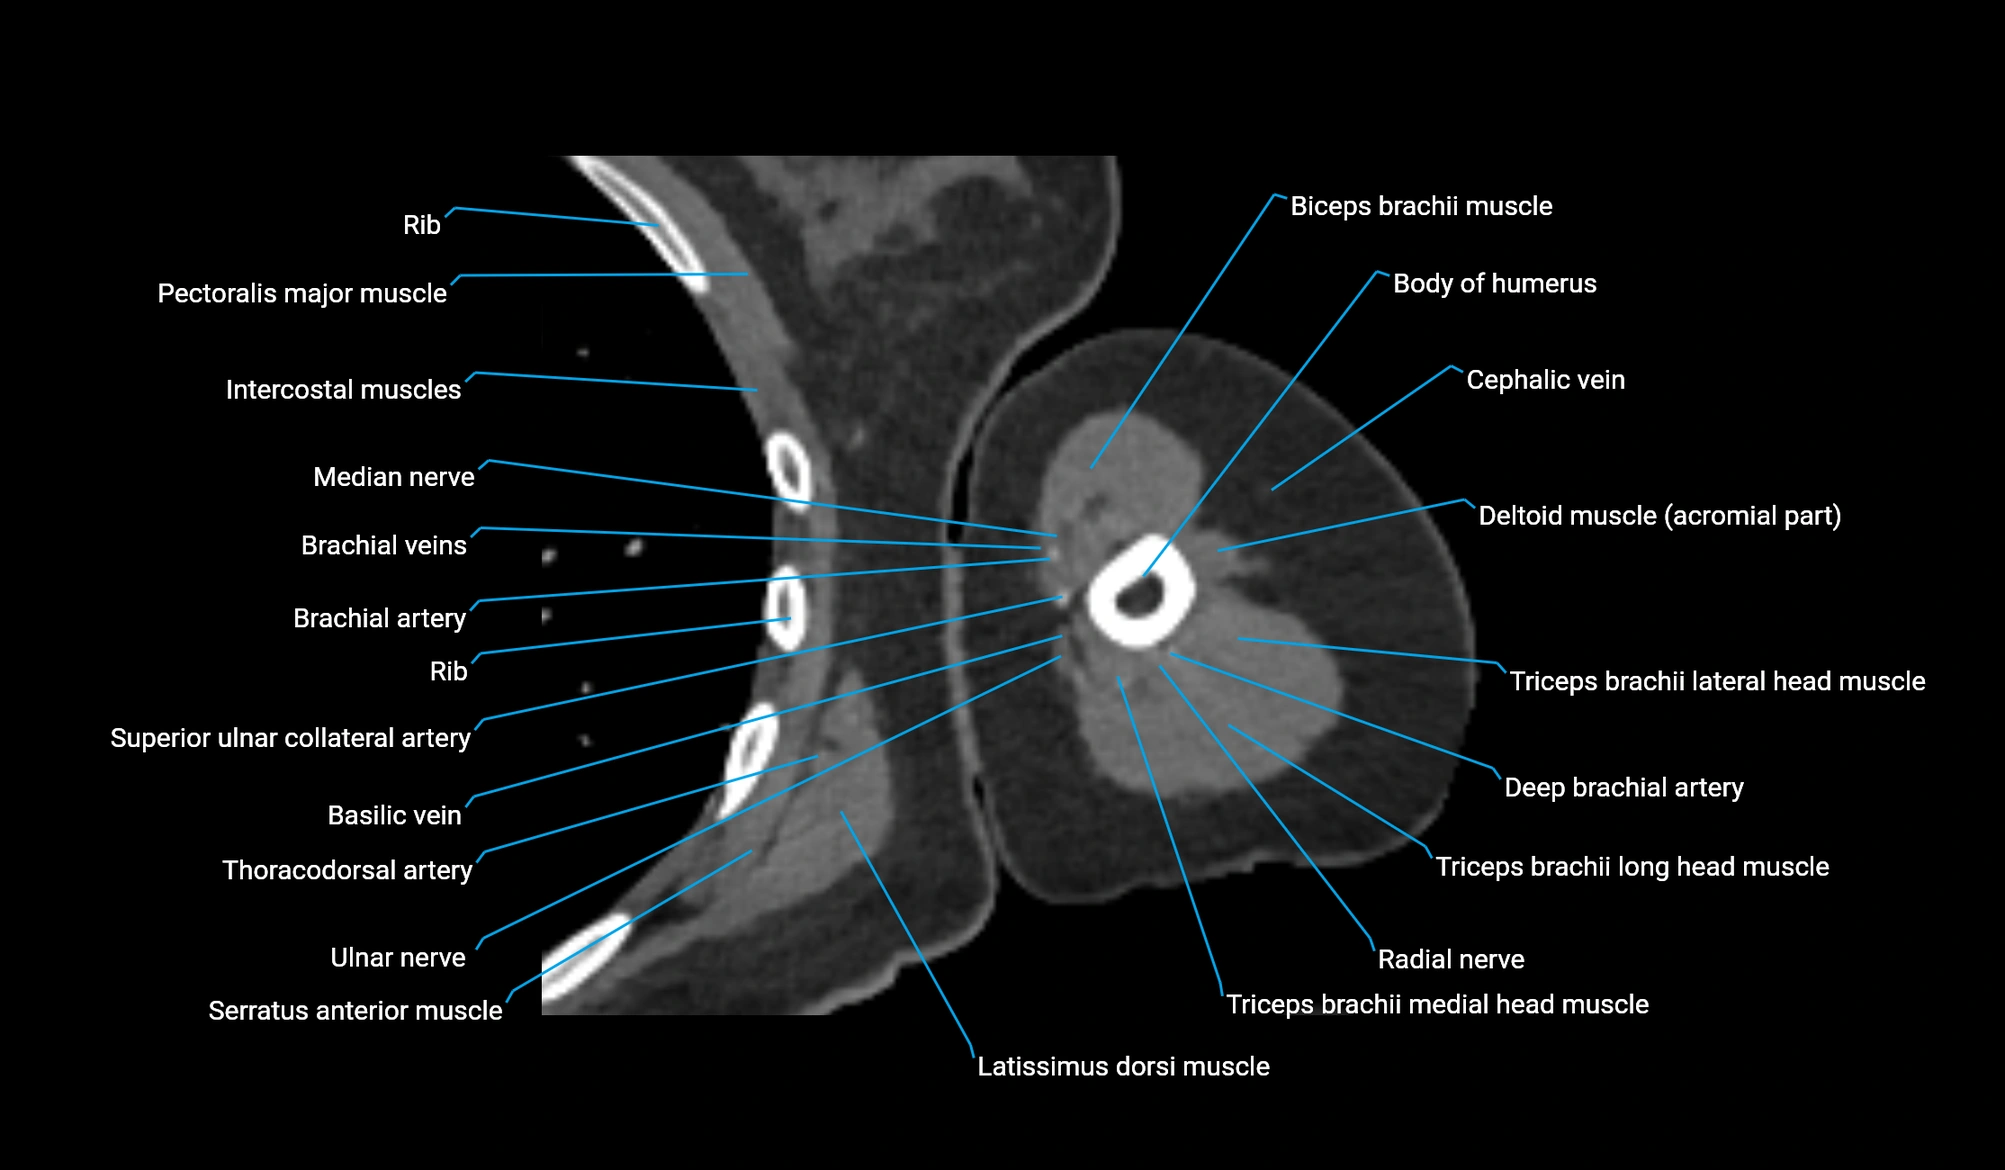

CT image